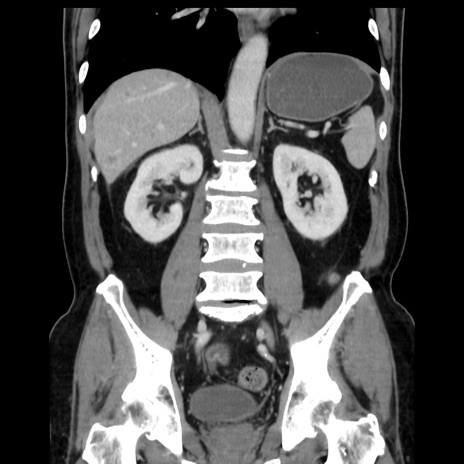

症例16(冠状断像)

【症例】 70歳代男性

【主訴】 腹痛、嘔吐

【現病歴】 約1ヶ月前より間欠的に腹痛と嘔吐あり、当院消化器内科を受診したところCTで多発する肝臓のLDAを指摘され、精査中であった。以降は消化器症状は安定していたが、2日前より嘔気と腹痛があり、同日より排便・排ガスが消失した。改善認めず、 本日、救急外来を受診した。

【既往歴】 大腸ポリープ切除後。

【身体所見】意識清明・会話良好、BT 36.3℃、BP 127/80mmHg、 P 80bpm、腹部:膨満あり、平坦・軟、上腹部正中および下腹部正中に圧痛あり、反跳痛なし、筋性防御なし。

【データ】WBC 7200、CRP 0.77